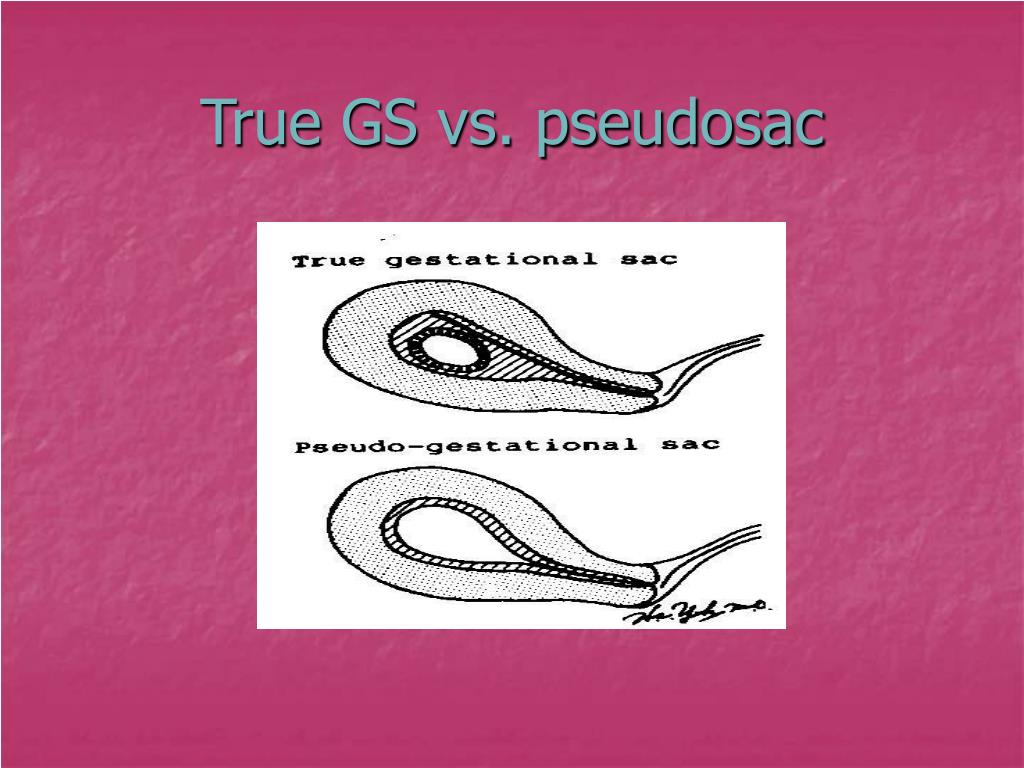

generally irregularly-shaped with pointed edges and/or filled with debris, sometimes referred to as 'beaking'. centrally located in the endometrial cavity, rather than eccentrically located within the endometrium. displaces the anterior and posterior endometrial cavity surfaces. does not demonstrate a yolk sac.

As opposed to a normal gestational sac, a pseudosac is typically located centrally and may fill the entire endometrial cavity and it also lacks the “double ring” sign. True gestational sacs will usually be slightly off-center and will have a detectable double decidual sign. True sacs also will eventually develop an internal yolk sac later followed by an embryo, but pseudosacs will have neither.